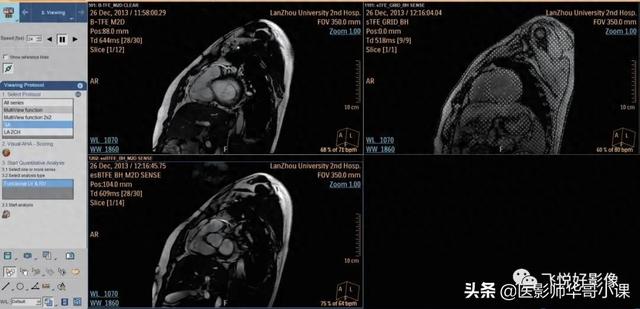

1)在心脏 MR 查看界面,选择一个功能性短轴多层多相位序列,一般选择左室短轴。为保证分析结果的准确性,选择一个整体左室从瓣膜到心尖均被扫描的序列。

图1.心脏MR查看界面